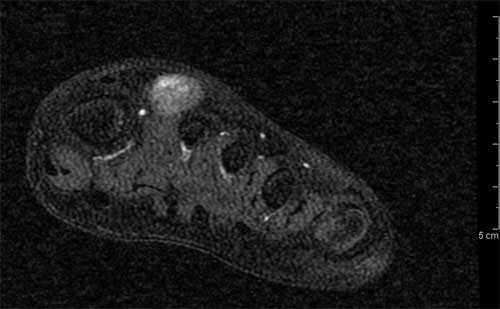

Figura 3. Presenza di flusso in parete. � stata effettuata una RMN con contrasto con acquisizioni multiplanari T1 e T2 pesate anche con tecnica di soppressione del grasso, con il rilievo di una formazione ovalare di 16 x 12 x 20 mm a margini regolari con iperintensit� di segnale centrale nelle pesate T1 e T2 dipendenti, e componente periferica sottile che subisce enhancement contrastografico, in apparente continuit� anatomica con struttura vascolare del fascio vascolo-nervoso dorsale, ascrivibile, in primis, a formazione vascolare o patologia vascolare dilatativa trombizzata (Figure 4, 5 e 6). ![]() |

Figura 4. Angio-RMN Scansione assiale T1 pesata SE. |

Figura 5.Scansione sagittale T1 pesata SE. |

Figura 6.Ricostruzione MIP. In questa breve sequenza di immagini si pu� notare il passaggio dal lume vascolare normale alla porzione ectasica e quindi di nuovo al calibro regolare (Figura 7). ![]() ![]() ![]() ![]() ![]() ![]() |

Figura 7. Serie di tomogrammi assiali STIR. L�intervento � stato condotto con l�induzione di una breve anestesia generale e l�escissione completa della formazione (Figura 8, 9 e 10).